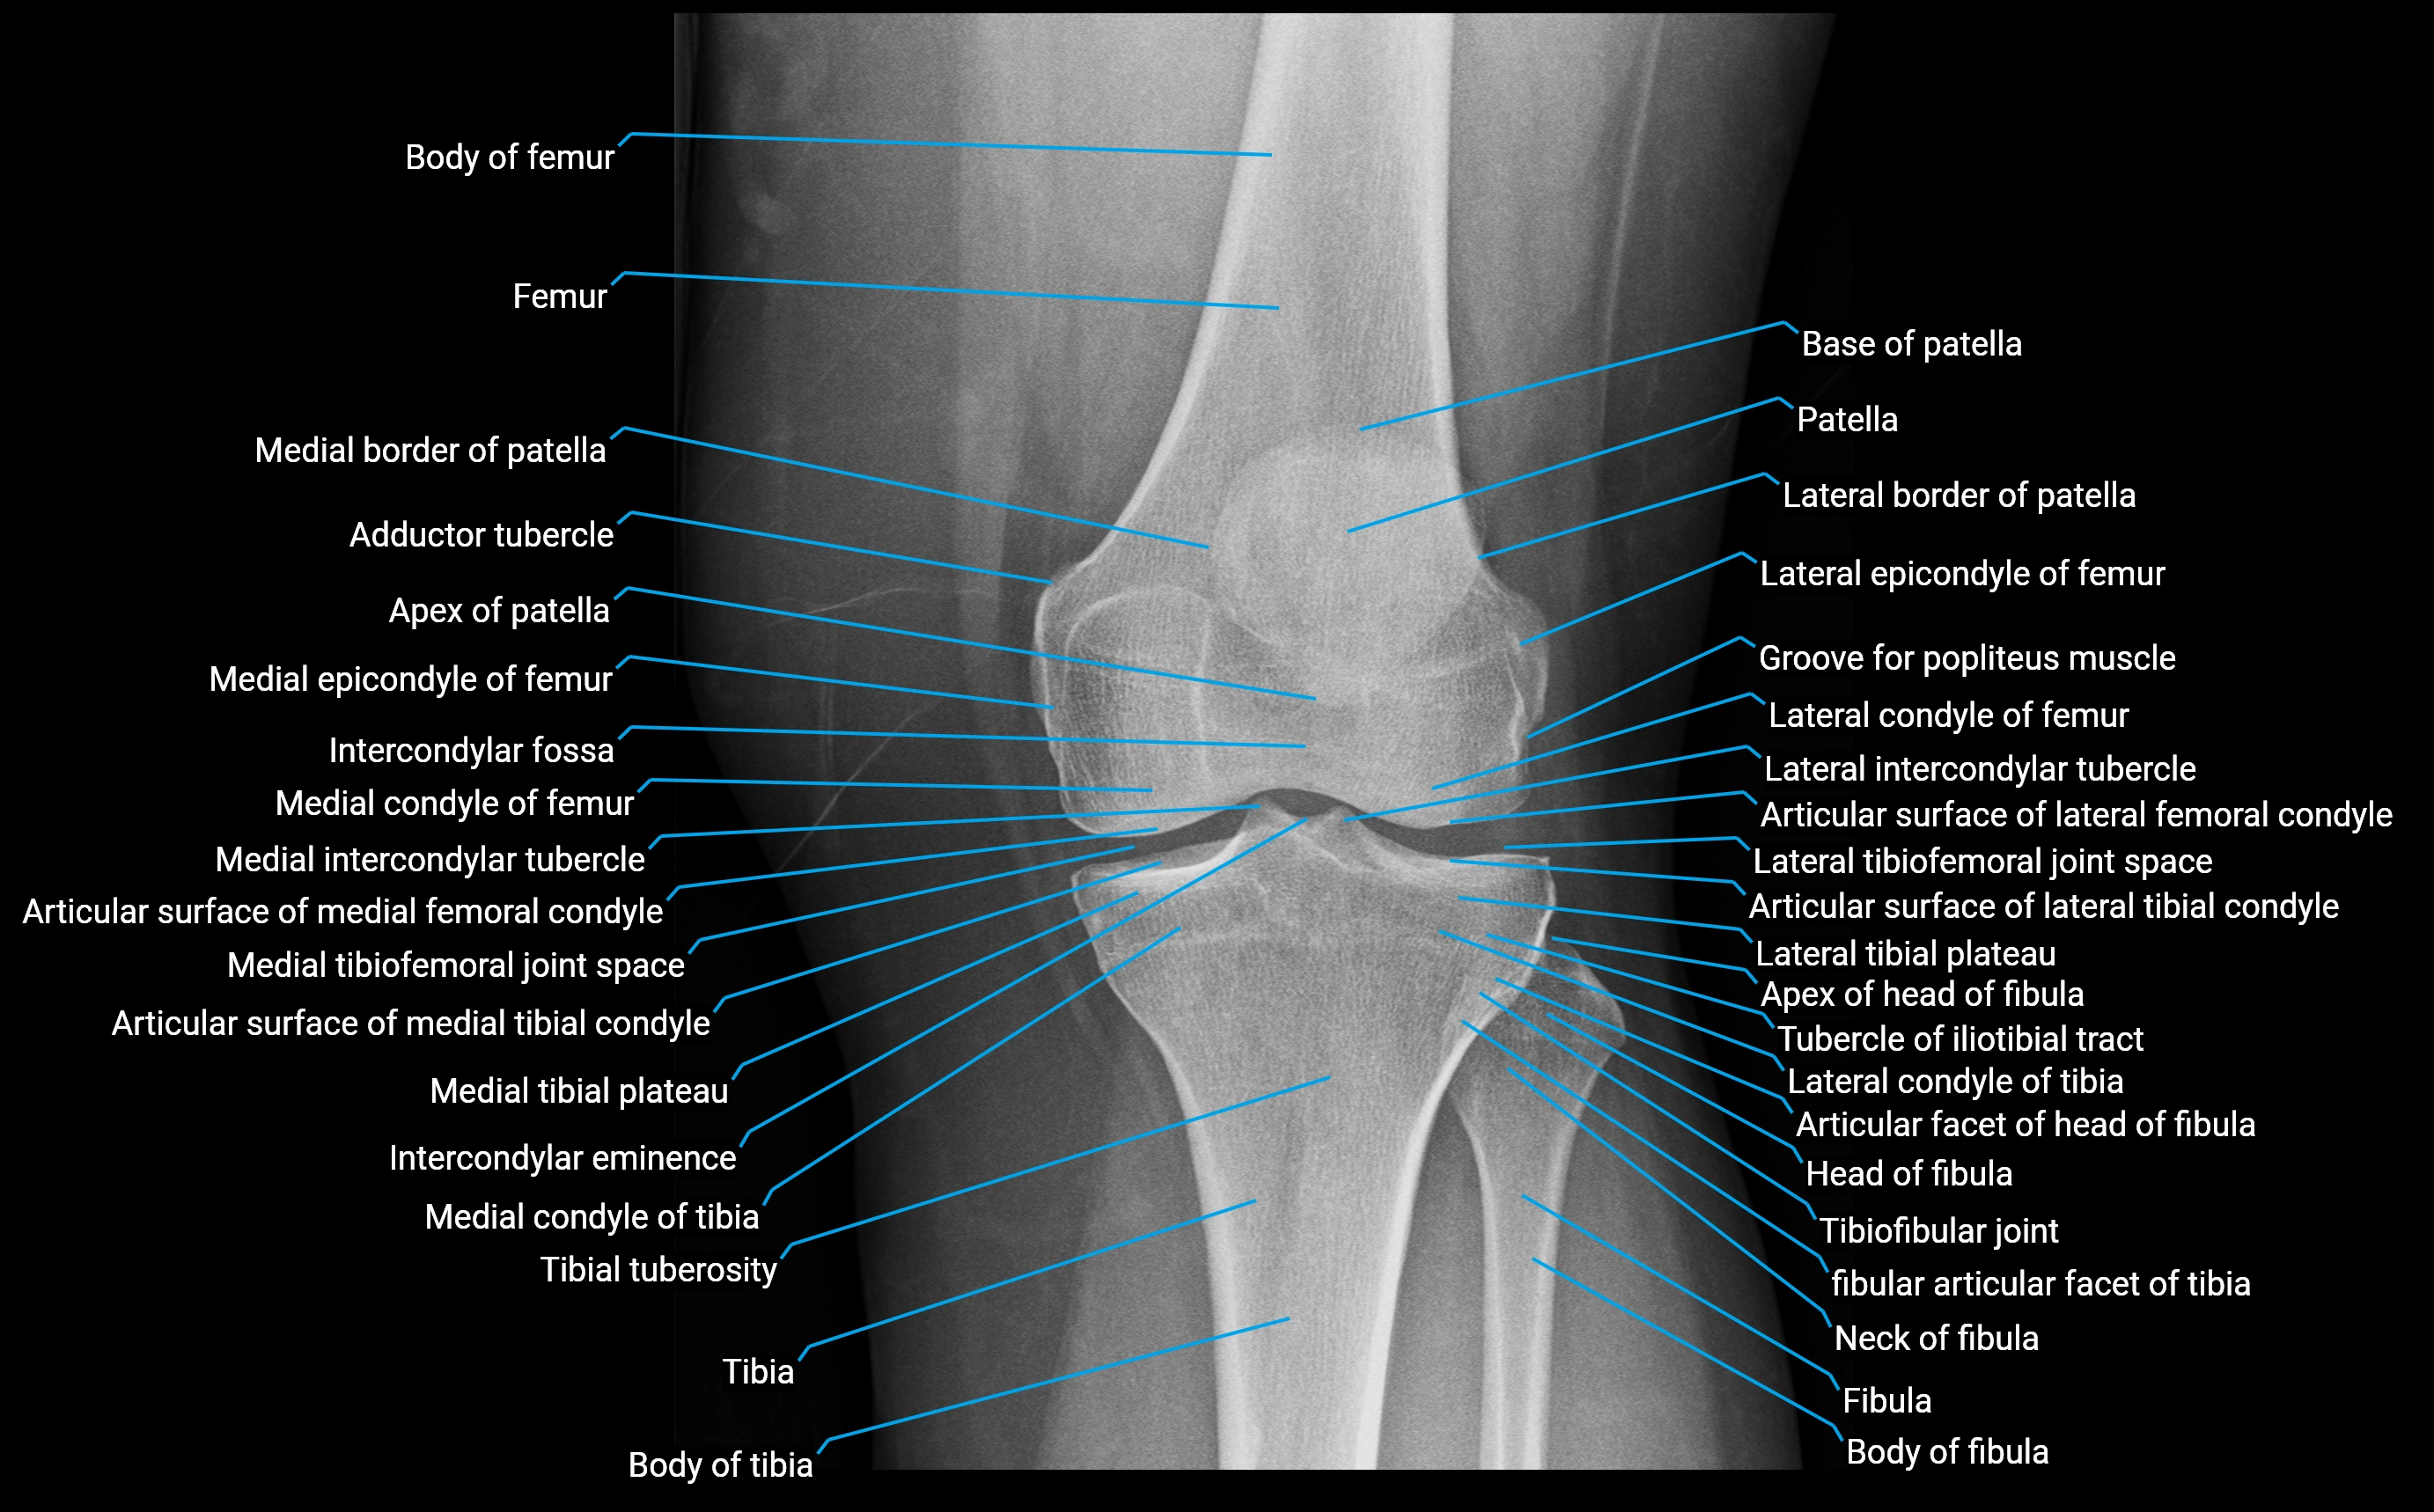

X-ray appearance

Plain radiographs (AP and lateral knee views):

• Adductor tubercle: Small bony prominence on the superior-medial aspect of the distal femur

• Cortical outline: Well-defined and continuous with femoral cortex

• Best visualized: On oblique or lateral projections